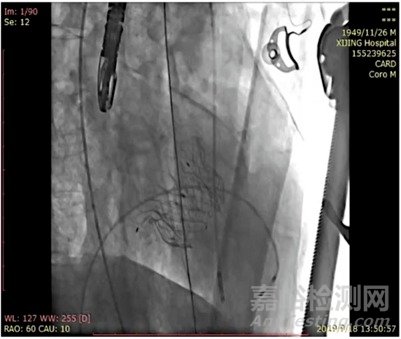

目前,Mi-thos®已成功于復(fù)旦大學(xué)附屬中山醫(yī)院、西京醫(yī)院完成多例探索性臨床人體應(yīng)用(Implement),應(yīng)用結(jié)果顯示,所有患者手術(shù)流程順利,術(shù)后瓣膜功能明顯好轉(zhuǎn),無嚴(yán)重并發(fā)癥發(fā)生,瓣膜反流消失,隨訪期臨床效果令人滿意,充分體現(xiàn)了Mi-thos®的安全性與有效性。

Mi-thos®成功釋放